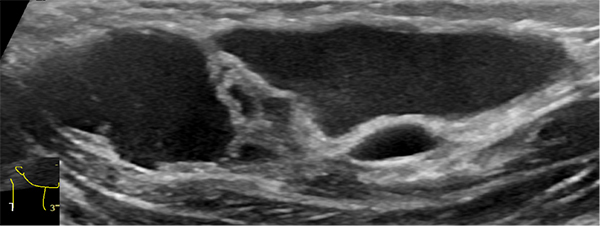

由于淋巴管畸形可发生在身体的任何部位,大多数发生在头颈部,其次为腋窝、纵膈及四肢。通常进行超声、磁共振、CT、诊断性抽液等检查,必要时依据情况进行穿刺活检,基本可以确诊。当怀疑患有淋巴管畸形时,应首先做超声检查,查清楚病变的部位、性质、大小及与周围组织的关系,评估是否需要治疗以及如何治疗。

淋巴管畸形超声:精准定位病灶部位范围以及与周边脏器的关系

超声难以确诊的病例,或病变周围结构较复杂(如在颈部、纵隔等部位)以及位置较深(如在腹腔、盆腔等部位)治疗难度大、风险高时,往往需加做磁共振检查,更精确评估病情。当影像学检查难以诊断时,也可行诊断性穿刺,若穿刺抽出淡黄色清亮淋巴液即可诊断为淋巴管畸形,若抽出陈旧性血液结合细胞学检查可诊断为淋巴管瘤伴出血。